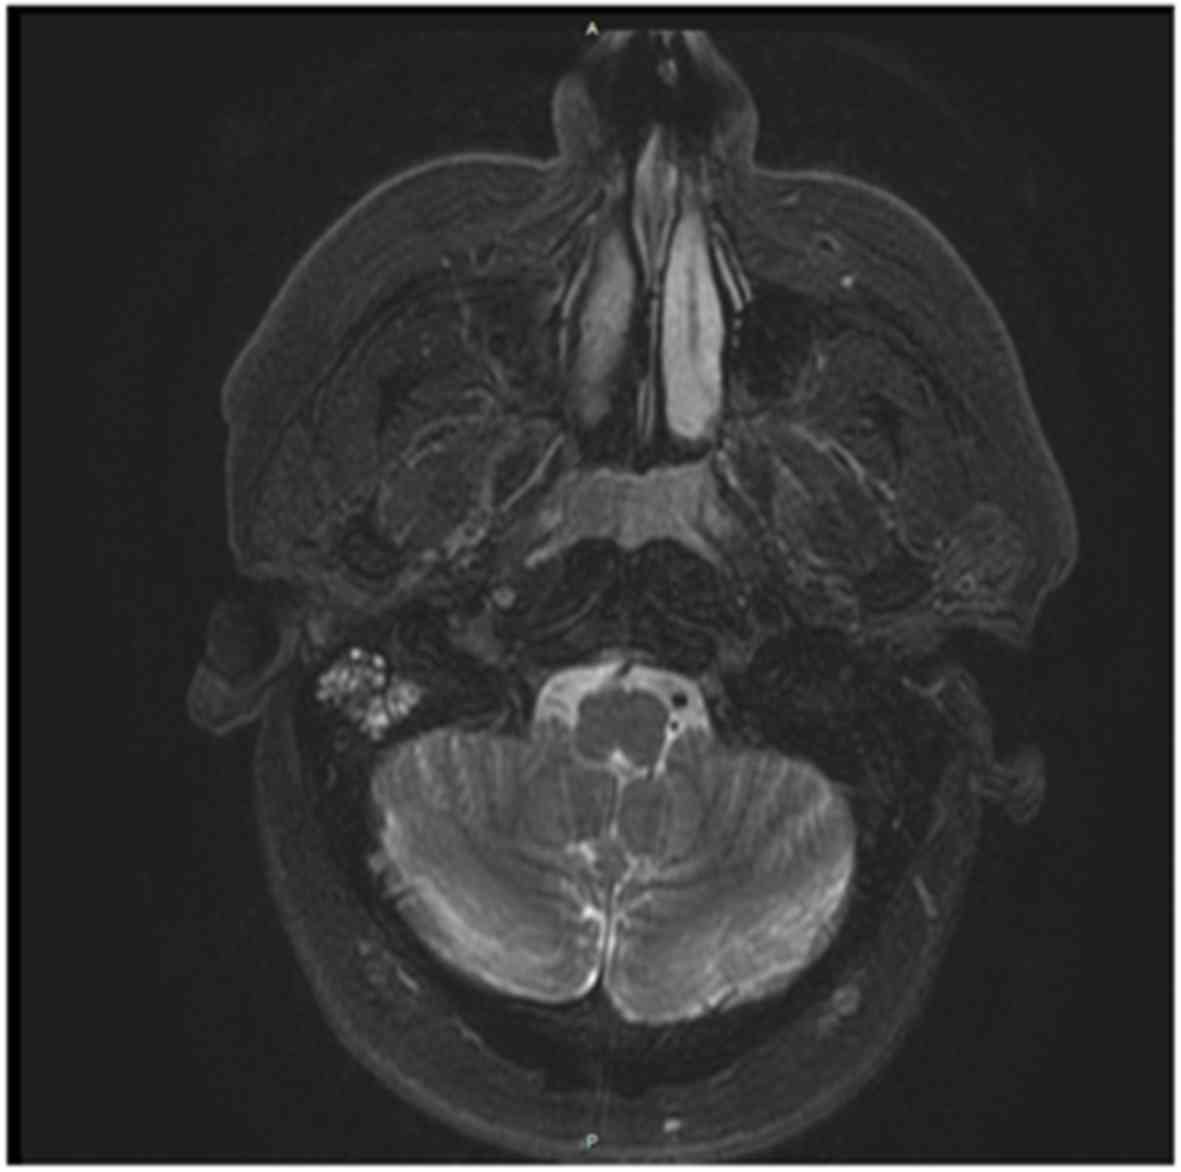

The patient underwent endoscopic examination of the upper airways that revealed a whitish, non-ulcerated, non-bleeding large mass in the posterior nasal cavity extending to the nasopharynx. Endoscopy was followed by magnetic resonance imaging (MRI) examination of the head and neck with gadolinium contrast, which confirmed the presence of a polypoid lesion sized 3.2×2.6 cm in the posterior nasal cavity, without invasion of the roof or posterior wall of the nasopharynx. There were no enlarged lymph nodes in the upper part of the neck (Fig. 1).

Figure 1.

Magnetic resonange imaging (MRI) of the head with gadolinium contrast revealed a polypoid lesion sized 3.2×2.6 cm in the posterior nasal cavity extending to the nasopharynx, without invasion of the roof or the posterior wall of the nasopharynx.